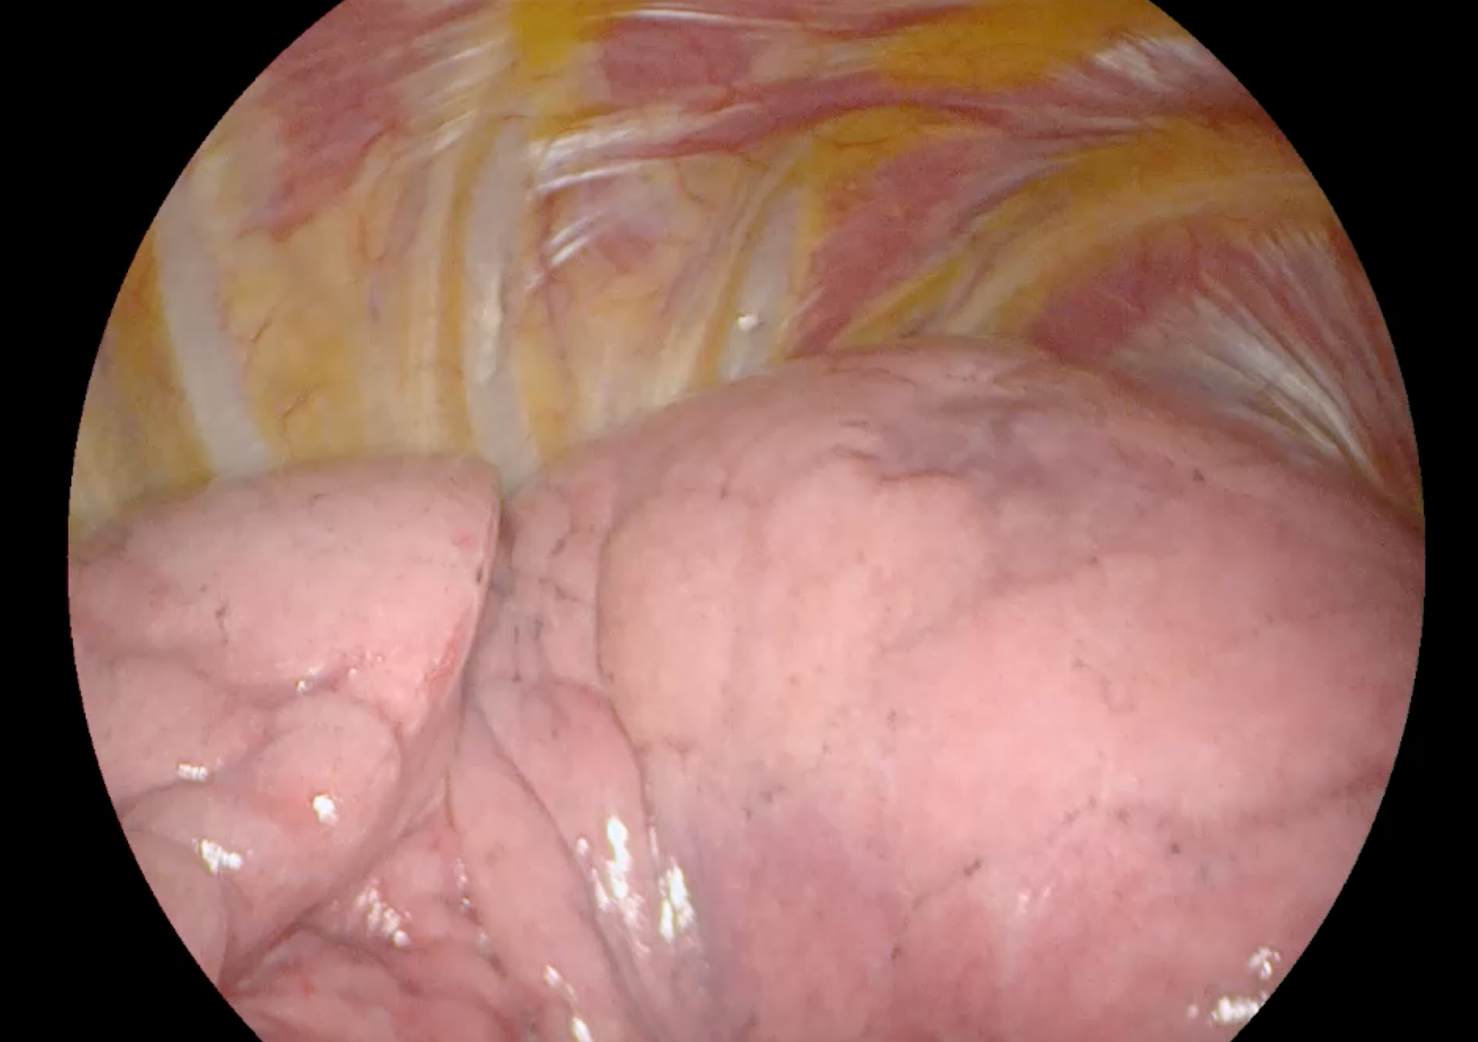

Lung visualization with standard white light

Lung tumor localization using abenacianine with NIR